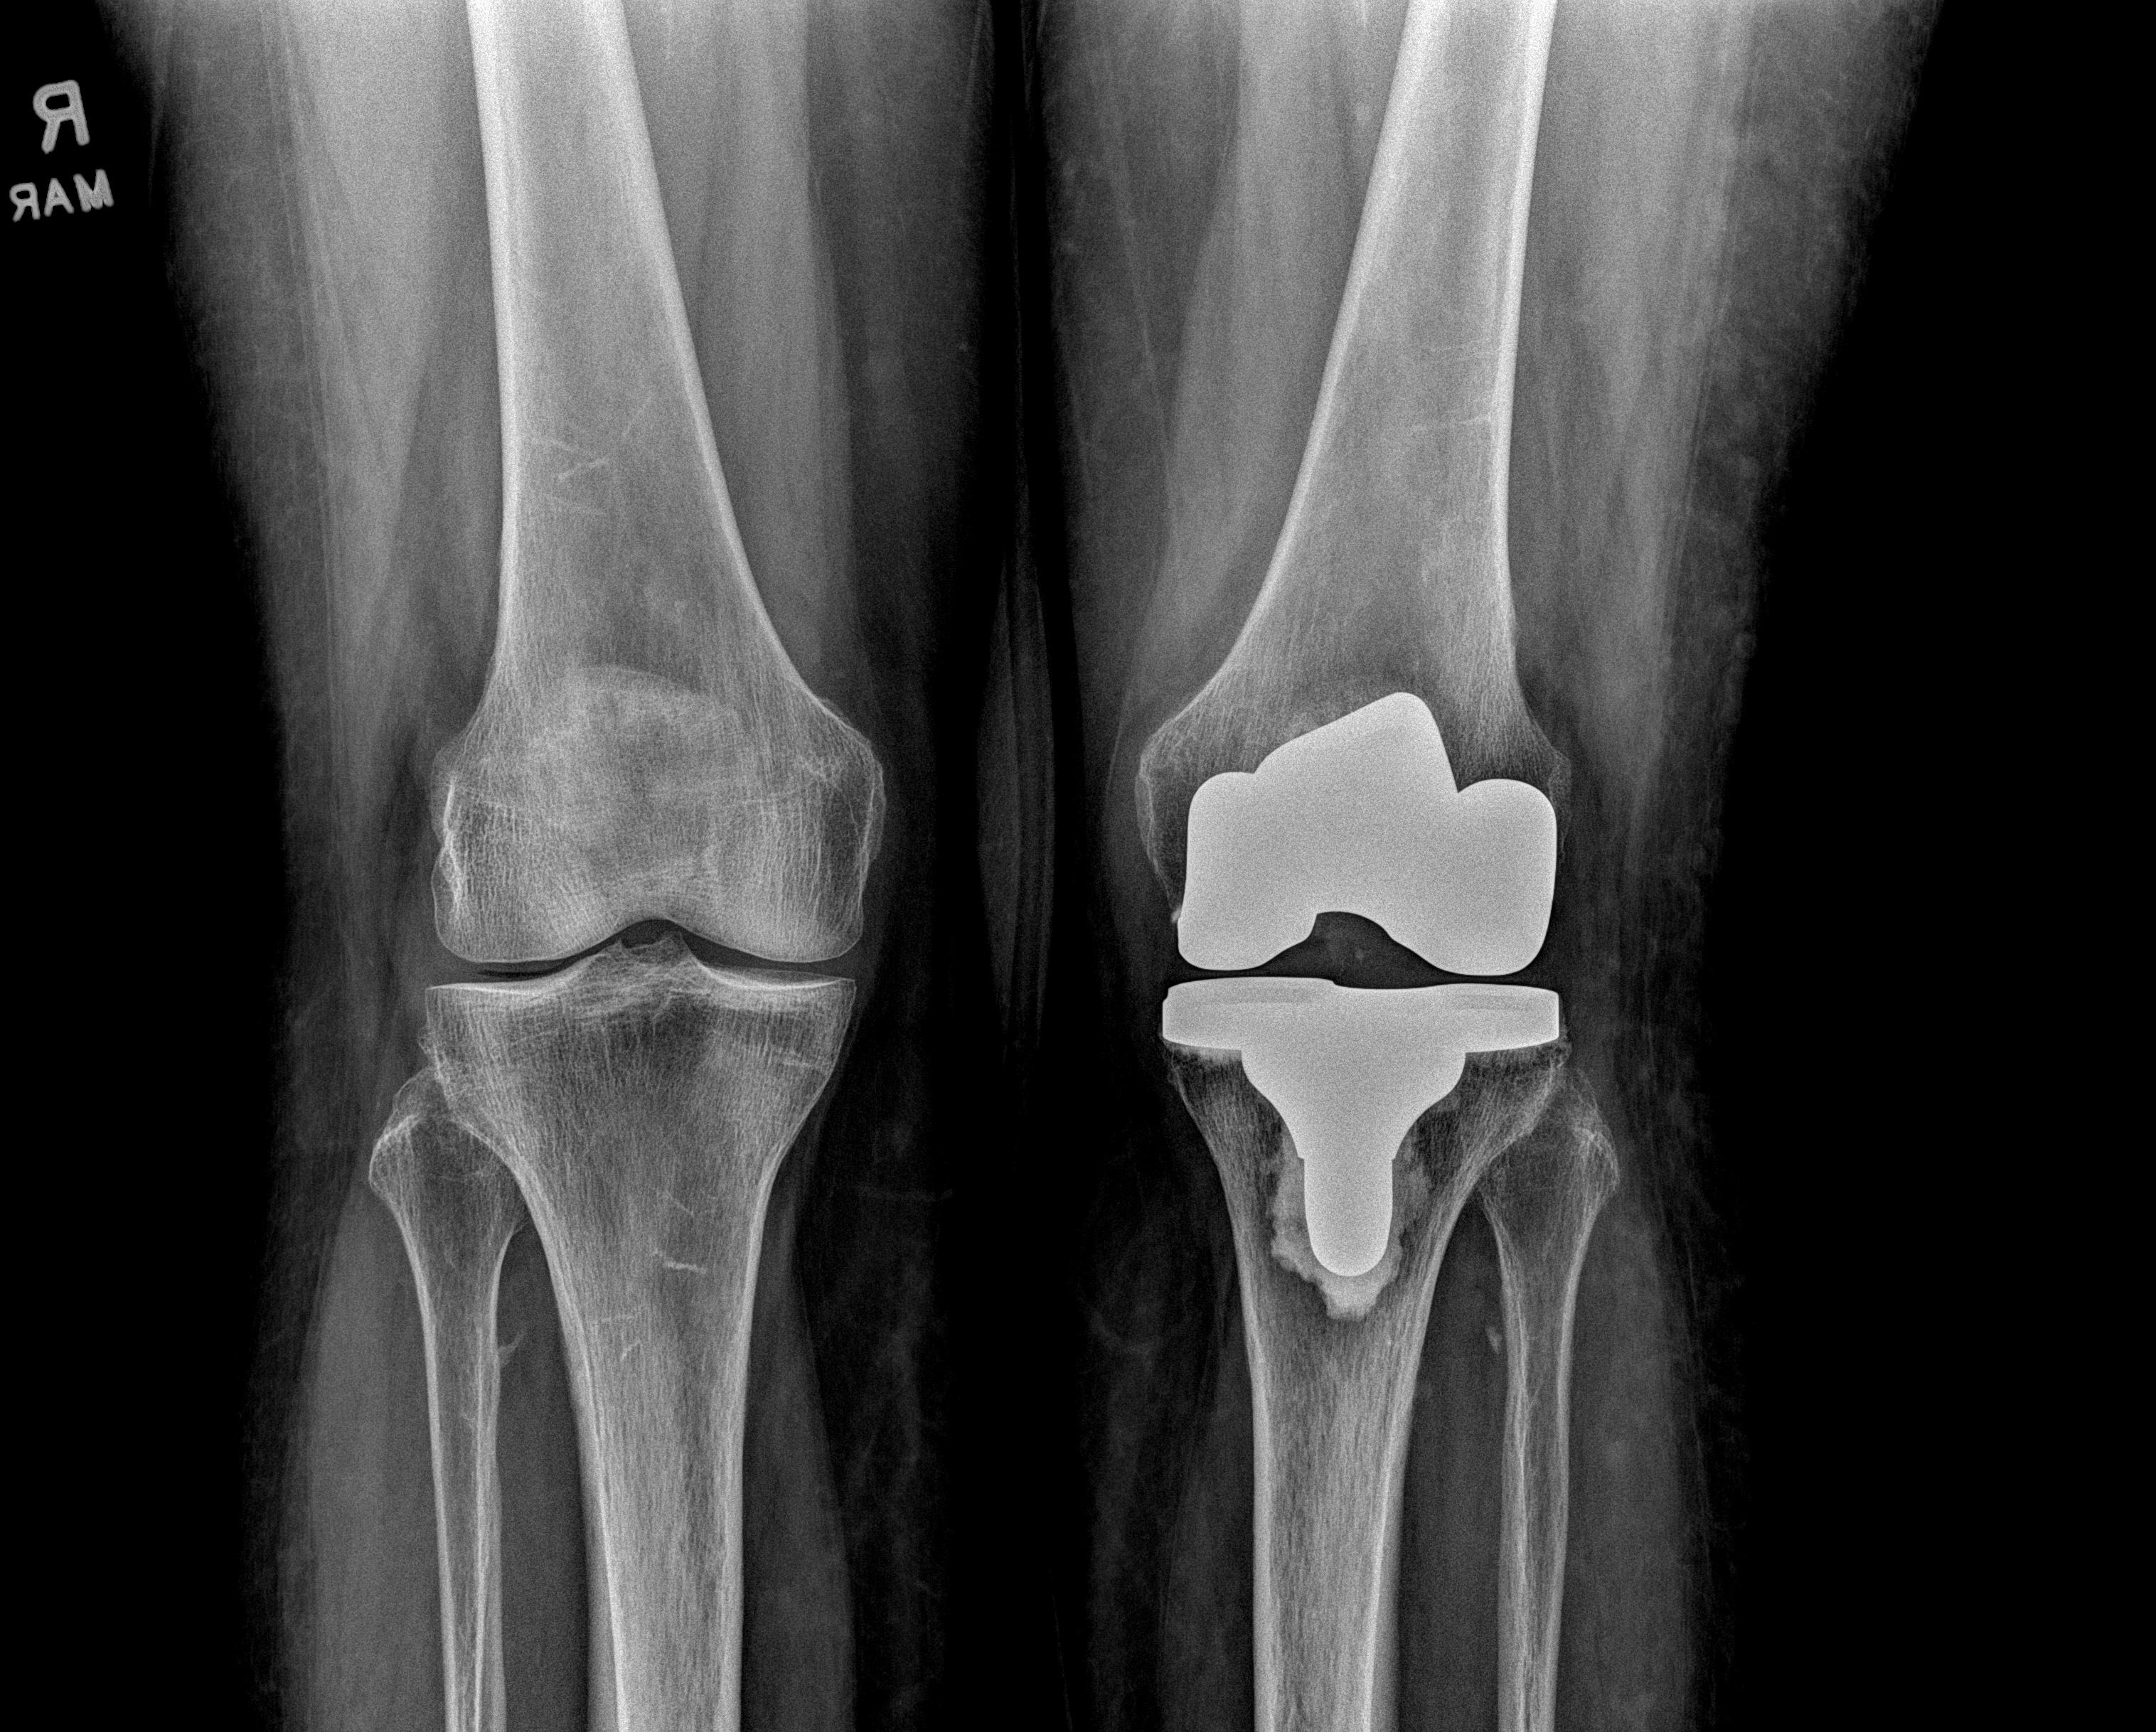

Figure 1: A patient following total knee replacement

Courtesy of Matthew Grosso, MD, FAAOS